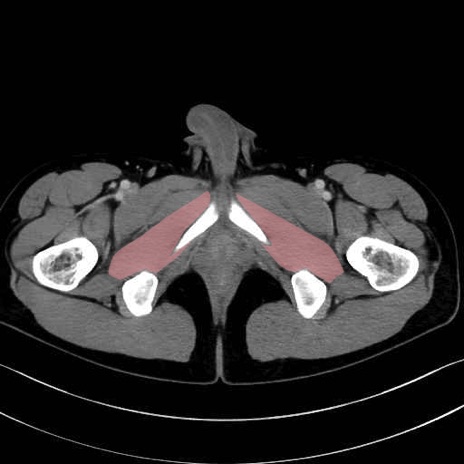

外閉鎖筋 (Obturator externus)